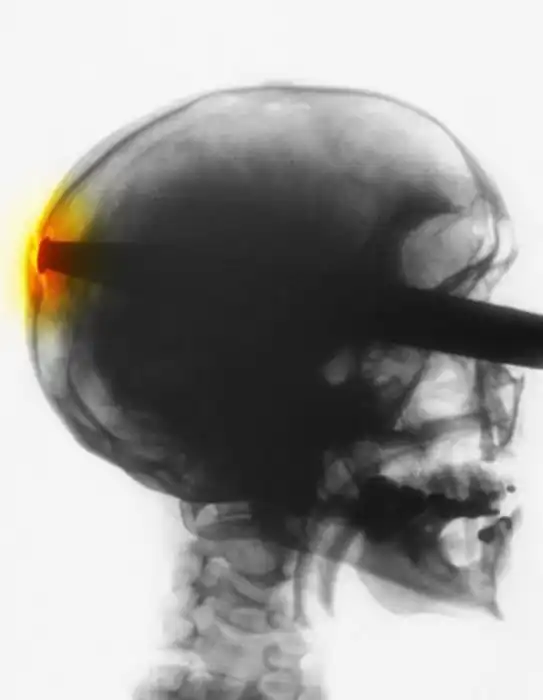

Жуткие рентгеновские снимки

Порой даже не верится, с какими странными и необычными повреждениями в травматологию могут поступить пострадавшие. Всю эпичность профессии врачей травматологии могут с легкостью подтвердить рентгеновские снимки.